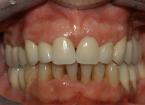

Riabilitazione completa superiore e settori posteriori inferiori

Paziente F, 52 anni, riabilitazione implanto-protesica completa superiore, ad appoggio dentale ed implantare. Riabilitazione implanto-protesica dei settori postero-laterali inferiori su denti naturali e su impianti.